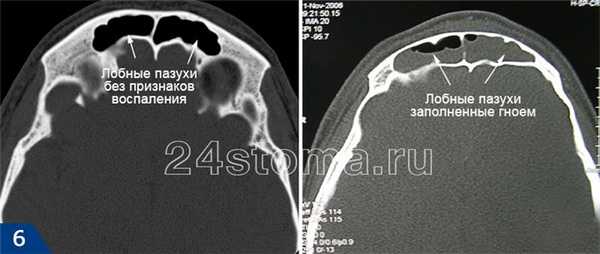

Фронтит на рентгенограмме и компьютерной томографии: фото

Рентгенография придаточных пазух носа позволяет выявить отёчность слизистой и скопление гноя в лобных пазухах.